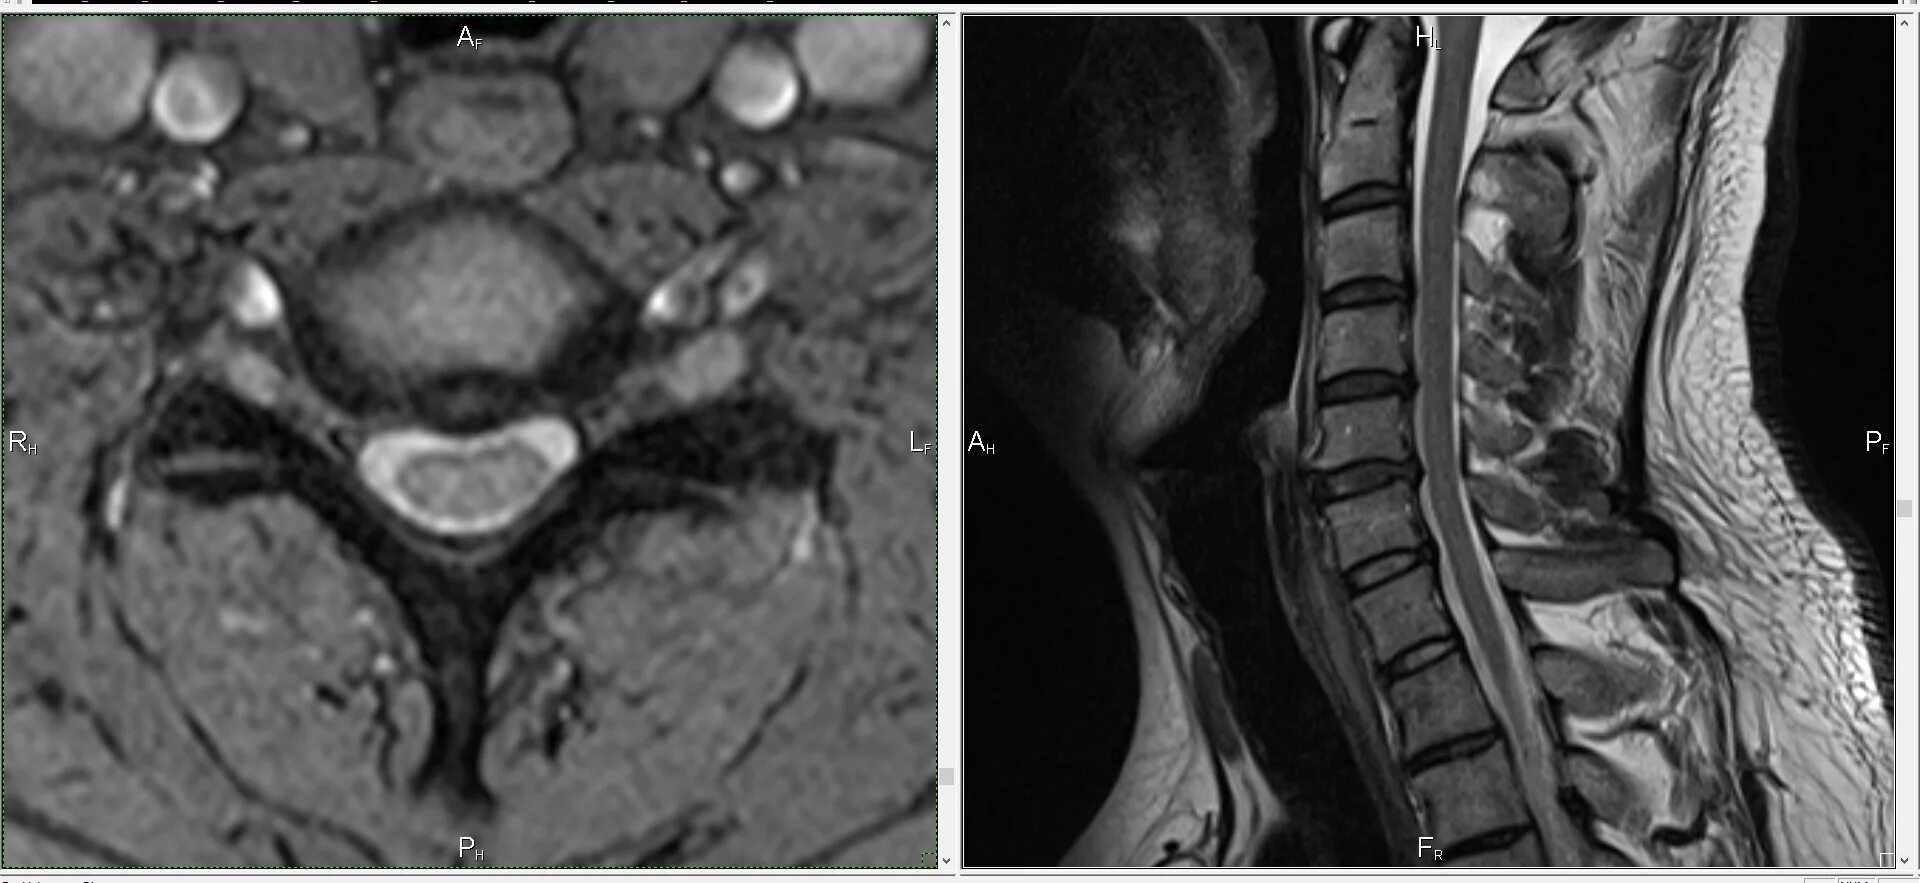

Кт тканей